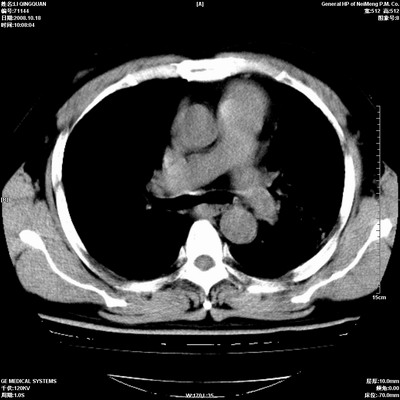

以下是引用duguo在2008-10-19 13:59:00的发言:[br]左肺上叶支气管狭窄,首先考虑中心型肺癌伴阻塞性肺炎\\肺不张.

以下是引用ybing在2008-10-19 12:58:00的发言:[br]左肺上叶阻塞性炎症-建议支气管镜进一步检查除外中央型肺癌

以下是引用随光逐影在2008-10-19 14:31:00的发言:[br]考虑左肺中央型肺癌并左肺上叶阻塞性肺炎,肺不张。